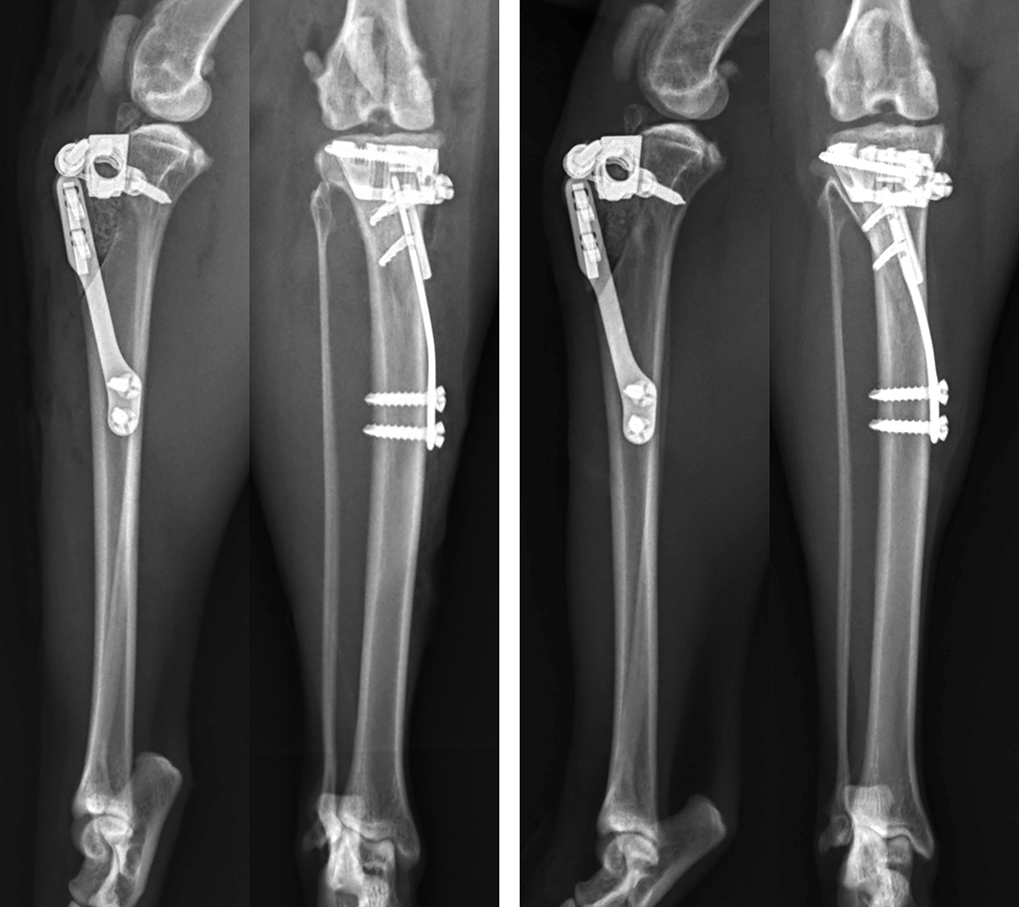

Mediolateral and craniocaudal radiographs of the left stifle of a seven-year-old domestic shorthair cat, which presented with cranial cruciate ligament rupture. The stifle was stabilised with a lateral fabellotibial suture using a suture anchor placed in the caudal aspect of the lateral femoral condyle and a bone tunnel just proximal to the tibial tuberosity as the paired attachment points.

Techniques aimed at achieving dynamic stabilisation by modifying femoro-tibial biomechanics in dogs have been suggested to potentially offer more favourable functional outcomes than techniques providing passive stability. An increased tibial plateau angle has been described as a risk factor for isolated CrCL rupture in cats (Schnabl et al, 2009) and tibial plateau levelling osteotomy (TPLO) has been described as a potential treatment option (Figure 5).

Matis et al (2010) were the first to report their experience with TPLO in cats. Twenty-nine TPLOs were performed in 28 cats, with follow-up being achieved in 22 cases. No arthrotomy or meniscal treatment was performed in these cases. A 12mm biradial saw was used for the osteotomy and mini T-plates or 2mm TPLO plates were used for stabilisation. In four cats, a lateral suture was also performed because the stability achieved by the TPLO was not felt to be adequate. Complications were encountered in three cats, all of which were attributed to technical errors, and two other cats had a suboptimal outcome due to a failure to recognise caudal cruciate ligament rupture at the time of TPLO, which led to ongoing stifle instability. Six weeks postoperatively, the majority of cats still manifested lameness and muscle atrophy. However, owners reported that, after a short while, cats were able to return to jumping and normal activity. The authors reported that TPLO in cats was technically more demanding than in dogs due to the relatively small anatomy and brittle bones of cats.

Mindner et al (2016) also reported their experience with TPLO in 11 cats. In this case series, joint exploration and meniscal treatment as necessary were achieved via either arthroscopy or arthrotomy prior to TPLO, with partial meniscectomy being performed if meniscal pathology was detected. A 12mm saw blade was used for every cat and 2mm or 2.4mm locking TPLO plates were used for stabilisation. Following surgery, all stifles were stable in cranial tibial thrust. Follow-up was achieved in all cases to 12 weeks and by 4-12 weeks postoperatively, lameness had either resolved or was graded as mild in all cats. Owners reported a high level of comfort and mobility in all cats at final follow-up, although, a positive “sit test” was reported in seven cats. Minor intraoperative complications occurred in five cats and minor postoperative complications occurred in three cats, but no major complications were noted. The preliminary results from both of these studies support the use of TPLO in cats, but further studies are required to compare clinical results following TPLO and other methods before conclusions can be made regarding whether one technique offers superiority.